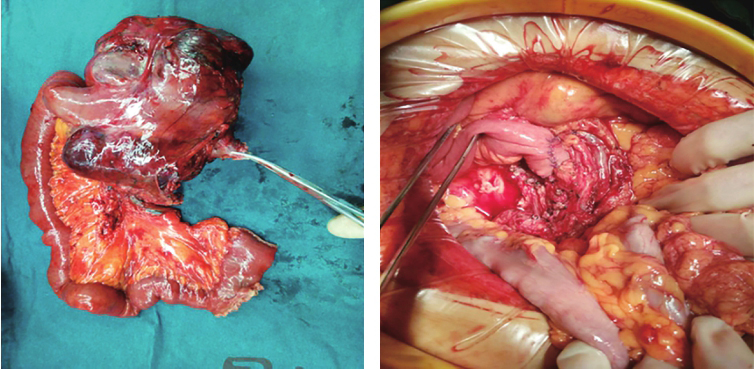

患者经输血补液,复查血常规示:血红蛋白73g/L。再次输入悬浮红细胞5U,于入院第四天在全麻下行剖腹探查术,术中探查见:上腹部一15.0cm×15.0cm肿瘤性病变,肿瘤似来源于十二指肠水平部,十二指肠及上段空肠包绕肿瘤,肿瘤有包膜,血供丰富,上达胰腺下缘,右侧达胰腺钩突部,左侧位于降结肠系膜后方,肠系膜上动静脉位于肿块右后方,肾静脉自肿瘤后方穿过,决定行十二指肠肿物切除术,手术过程顺利,术后标本及腹腔情况见图2。

术后病理:(十二指肠水平部)胃肠间质瘤。肿块大小约14.0cm×10.0cm×6.0cm,细胞梭形、轻度异型、核分裂象>5个/50HPF;送检肠管两手术切缘未见肿瘤累及。改良NIH危险度分级:高危。

图2 术后标本及腹腔情况